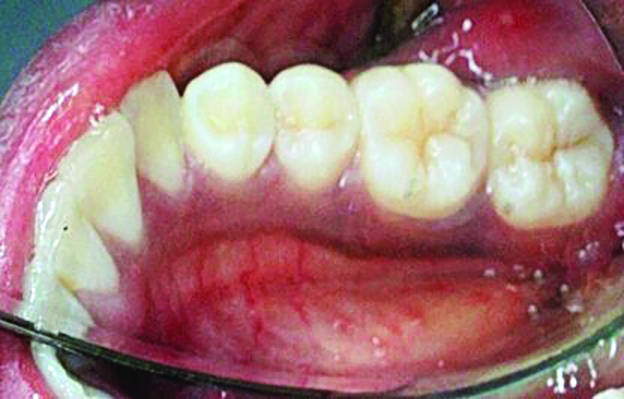

Fig 7. Lingual attached gingiva in a female subject: Fig 7 = left side, Fig 8 = middle, Fig 9 = right side.

Figure 7

Fig 8. Lingual attached gingiva in a female subject: Fig 7 = left side, Fig 8 = middle, Fig 9 = right side.

Figure 8

Fig 9. Lingual attached gingiva in a female subject: Fig 7 = left side, Fig 8 = middle, Fig 9 = right side.

Figure 9